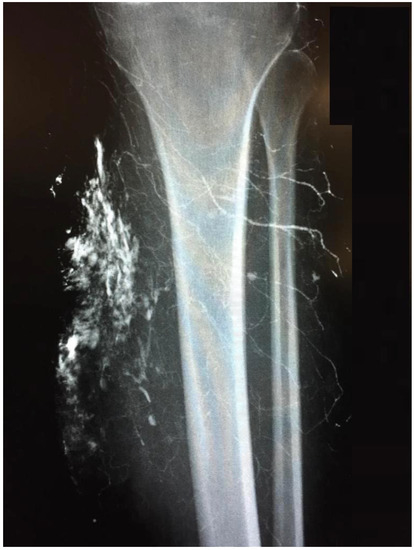

The indication for surgical treatment was a persistent pathology of the musculoskeletal system in the lower extremity. Either because conservative therapy was not successful, or ulcerations were present. Conservative therapy included sufficient medical treatment for RAD and physiotherapeutic therapy and provision of assistive devices where necessary. When surgical treatment was indicated, a preoperative evaluation was performed. Imaging with CT, MRI in conjunction with angiography, and lymphography were used (Figure 1 and Figure 2). Surgeries were performed under steady-state conditions and single-shot antibiotics. The supplies were primarily not joint-related but addressed periarticular tissue.

Figure 1. Lymphography of a chronic ulcer of the left tibia. ©UKGM Giessen.